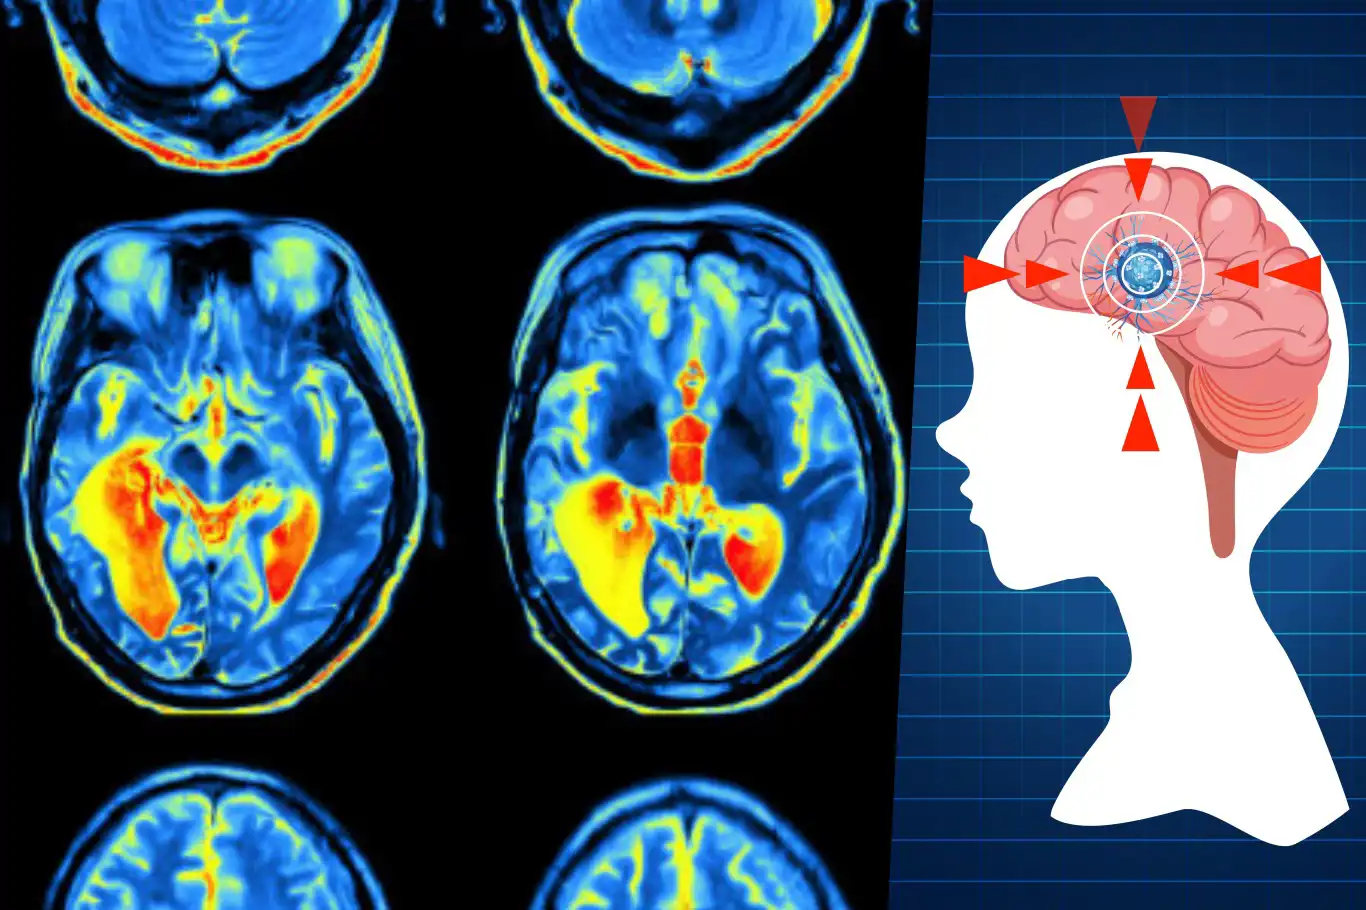

The study analyzed brain scans from around 4,000 people up to the age of 90 to map the connections between neurons. Researchers found that brain development is not a smooth, continuous process but occurs in distinct stages.

Childhood (birth to age nine): The brain rapidly grows in size but also prunes excess neural connections, or synapses. During this period, the brain operates inefficiently, akin to a child meandering through a park rather than taking the most direct route.

Adolescence (ages nine to 32): Beginning at age nine, the brain undergoes a period of heightened efficiency, reorganizing its connections in a “ruthless” pruning process. This stage, which lasts into the early 30s, is also when individuals face the highest risk of developing mental health disorders. Researchers note that adolescence extends far beyond the teenage years, peaking in early adulthood.

Adulthood (ages 32 to 66): This is the longest phase, marked by stability and a gradual reversal of the efficiency gains made during adolescence. Cognitive performance and personality traits typically plateau during this period.

Early Ageing (ages 66 to 83): At 66, the brain begins to reorganize into more tightly connected regions rather than functioning as a fully integrated network. Although the study focused on healthy brains, this stage often coincides with the onset of dementia and other age-related health conditions.

Late Ageing (83+): The final phase shows even more pronounced changes in brain connectivity. Researchers faced challenges in studying this age group due to the scarcity of healthy brains available for scanning.